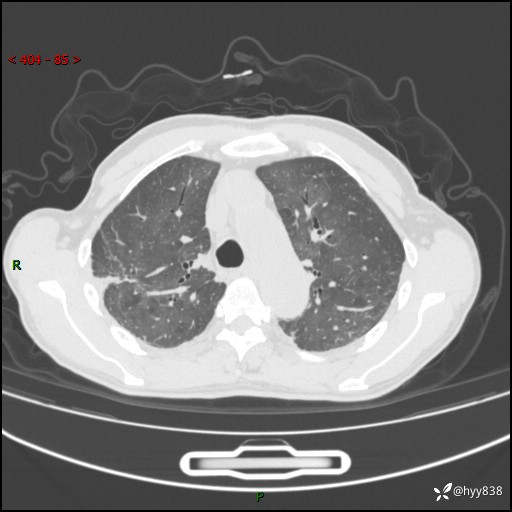

肺结节入院,CT却发现肺部弥漫性病变,what happened---(有结果)

主诉:检查发现左上肺结节4天

简要病史:患者于2024-01-15当地市人民医院胸部CT提示:左肺上叶(69)结节,最大截面约1.0 x 1.2cm,肿瘤病变待排。现患者活动后呼吸困难,自述平地行走200m后胸闷气喘,不伴咳嗽咳痰、头晕、恶心、呕吐等不适,未行特殊处理。现患者为求进一步治疗,于我院就诊,门诊拟“左上肺结节”收入院。 自患病以来患者食欲差,精神、睡眠尚可,大小便正常,体重近1月来下降5kg左右,体力明显减轻。

辅助检查:CT

胸部CT平扫

不是讨论肺部结节